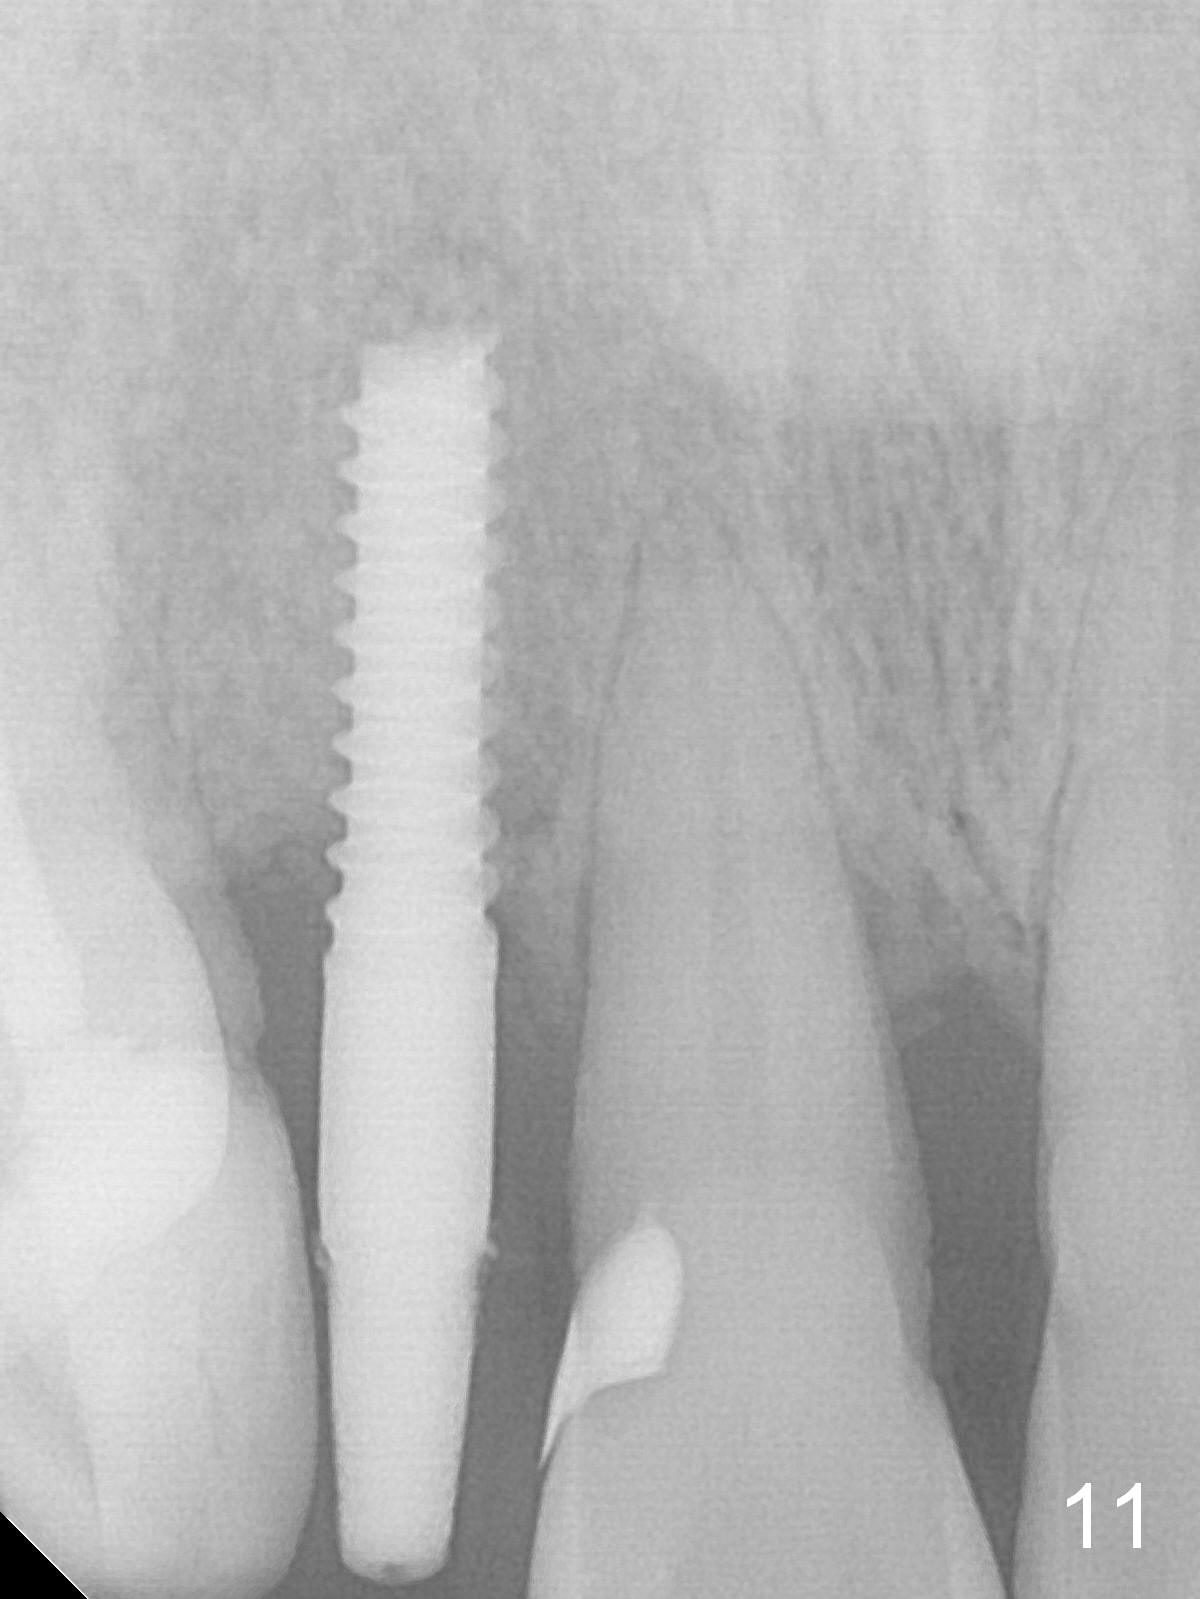

Apical Buccal Plate Perforation

Preop exam shows the apparent wide ridge at #7 (Fig.1). What is ignored preop is the concavity in the apical buccal region (Fig.2 *). When a 3x16(4) mm 1-piece implant is being placed (Fig.3 *, flapless), the apical buccal plate vibration is felt. The biggest mistake is that initial osteotomy is ~ 6 mm shy of the implant length, partially because of 6 mm gingival height. Since the tooth #6 is symptomatic after RCT with paste overfill (Fig.4 >), apicoectomy is contemplated at #6 with exploration of the buccal plate at #7 (Fig.5). Since the implant appears to be long enough, implant apical resection is performed (Fig.6). Since there is coronal thread exposure due to previous periodontitis (Fig.7 <), bone graft is placed in these 3 defective areas after decortication.

Extending the initial osteotomy to the full length of the implant is critical. If perforation is detected early, the trajectory can be changed. Incision should be made if there is no CBCT study. The incision heals 1 and 4 weeks postop (Fig.8,9). The patient returns for final restoration 6 months postop. Apical defects appear to have healed at #6 and 7 (Fig.10,11). Fig.12 is taken 11 months postop and 5 months post cementation. The patient has an accident 9 months post cementation. In fact the implant is alright, while the tooth #6 fractures and #8 subluxates.